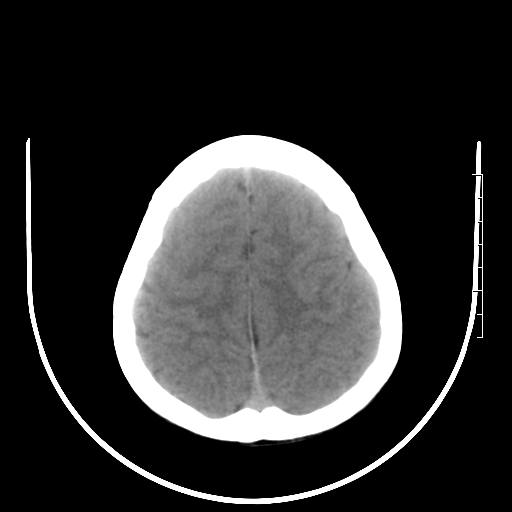

标题: PED3377:m、9y,恶心、呕吐,每月发作2-3次。 [打印本页]

标题: PED3377:m、9y,恶心、呕吐,每月发作2-3次。

颅脑ct轴位平扫颅内未见明确异常。

头颅ct平扫未见异常

颅脑ct平扫未见异常。